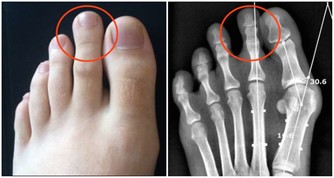

六、腸胃最怕涼

夏天是腸道疾病的高發期,專家建議,這個季節少吃太涼的東西,尤其早晨起床時和晚上臨睡前。

為了及時給“腸胃”保暖,吃涼拌食物時,不妨加點姜或芥末,可以暖胃、殺菌。